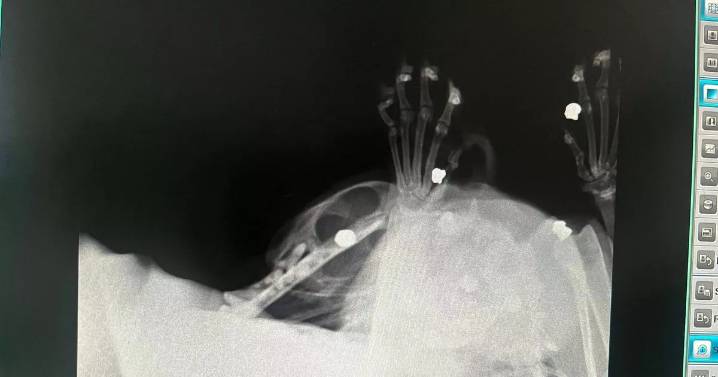

Brutal X-ray images have revealed pellet bullets lodged in a rescue cat's neck after being 'shot eight times' in Salford .

The vet later confirmed the lumps were in fact pellet bullets and that Marley had been shot eight times before being rescued from Salford.